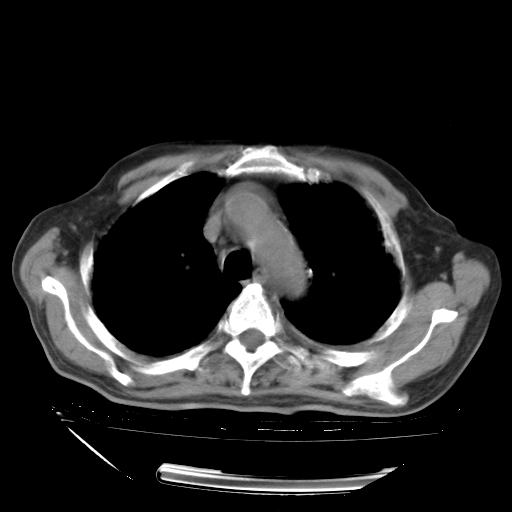

甲强龙80mg/日+抗结核治疗(异烟肼+利福霉素+乙胺丁醇)10天。复查肺部CT。

治疗10天肺部CT

94186 3 10.bmp

94186 3 11.bmp

94186 3 12.bmp

94186 3 13.bmp

94186 3 14.bmp

94186 3 15.bmp

94186 3 16.bmp

94186 3 17.bmp

94186 3 18.bmp

94186 3 19.bmp